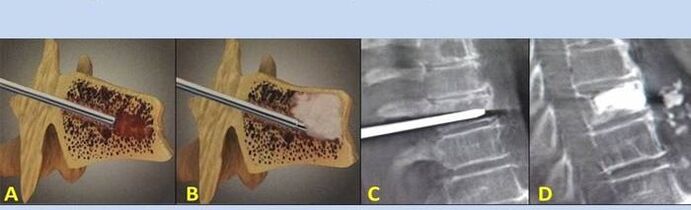

- Nucleoplastia – extirpación del núcleo del disco intervertebral. La operación alivia la presión sobre las terminaciones nerviosas.

- Vertebroplastia por punción – método de estabilización de las vértebras. Durante el procedimiento, el médico llena las cavidades de la columna con cemento óseo.